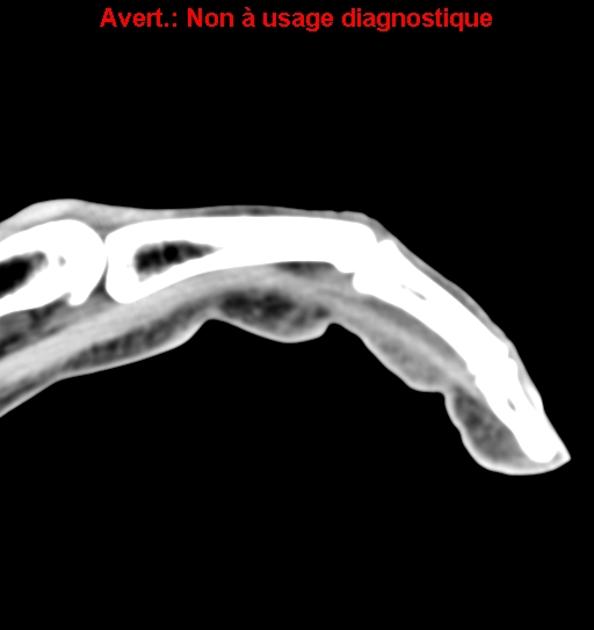

From pacs.de

annular pulley lesions pacs Pulley Lesion Hand Pulley lesions are most commonly seen in the ring and middle fingers and may be diagnosed in up to 30% of finger injuries. Fixed contracture of the pip joint may result if timely. Mr imaging is a powerful method for evaluating acute and chronic lesions of the stabilizing articular elements (volar plate and collateral ligaments) of the fingers and. Diagnosis. Pulley Lesion Hand.